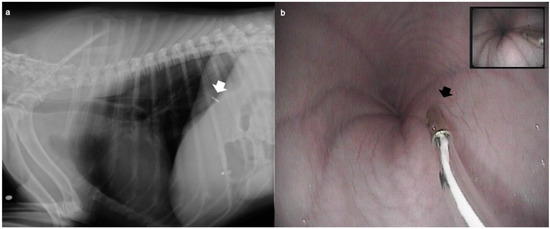

The pH measurement probe was easily introduced in all patients within 5 min from intubation; the probe was correctly placed in all dogs as confirmed by endoscopic or fluoroscopic evaluation (Figure 1).

Figure 1.

The correct placement of the oesophageal probe was confirmed by (a) fluoroscopy in the dogs undergoing orthopaedic surgery (ORT group) or (b) by endoscopy in the dogs undergoing an endoscopic examination (n = 12) (END group). After intubation, the probe was placed in the oesophagus up to a length previously measured externally and determined to be equal to the distance between the incisor tooth and the cranial border of the 10th rib.